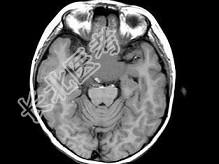

- 单项选择题女,8岁, 头痛、左侧肢体麻木十余天,根据所提供图像, 最可能的诊断是 ( )

A、表皮样囊肿

B、颅咽管瘤

C、垂体瘤

D、胶质瘤

E、蛛网膜囊肿